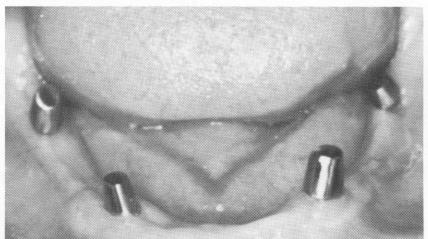

Fig. 11-142. The excellent healing around each implant post is evident 2 weeks postoperatively. Note also the lack of parallelism, which resulted from the fact that these earlier types of blades were cast in cobalt-chrome, which could not be bent. Also, the hardness of the metal made it extremely difficult to parallel the posts with grinding stones. In spite of this, note the excellent condition of the tissues around each post.

2 Excellent healing around mandibular implant posts postoperatively